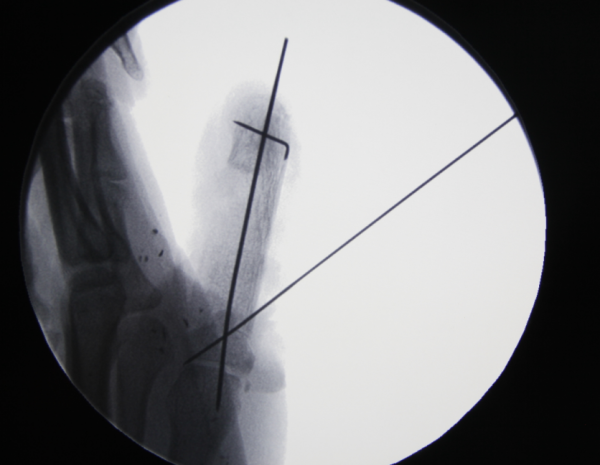

前天值班,来了7个再植的病人,初学者来省立医院进修是个很好的选择。这是其中一个。示指旋转撕脱,近侧指间关节处离断,保关节再植。

非断面截骨

x线

术后即刻,血管撕脱太厉害,动静脉还是移植了。